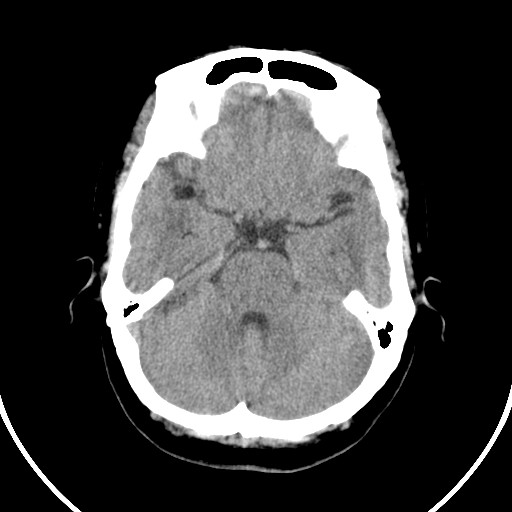

标题: CT21850:女,56岁,右中指淤肿,右手麻痹1天

女,56岁,右中指淤肿,右手麻痹1天

右枕叶低密度区伴硬膜下血肿——增强扫描或mri。

双侧侧脑室额角旁对称性略低密度影,边缘模糊,无占位效应,考虑轻度脑白质稀疏症(病人有高血压吗).,右枕叶低密度影多为伪影,不放心薄扫一下.

右枕叶条状低密度影不应该忽略可能极具意义